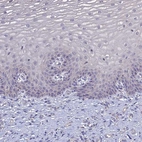

Immunohistochemical staining of human thyroid gland shows moderate positivity in apical membrane in glandular cells.